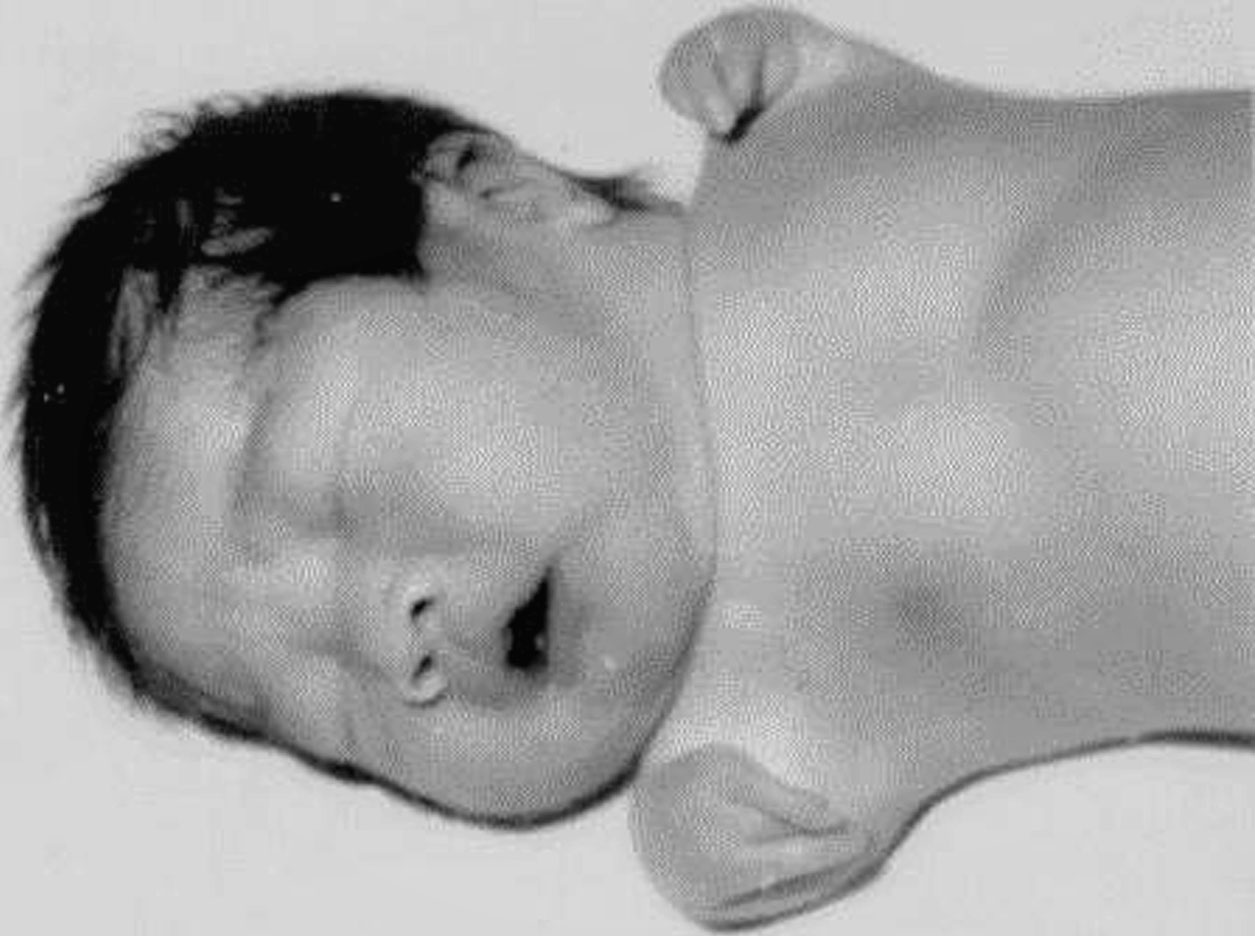

图1-2-12 完全性“海豹手”畸形

上臂及前臂未发育,手直接附在肩上(图1-2-12)。